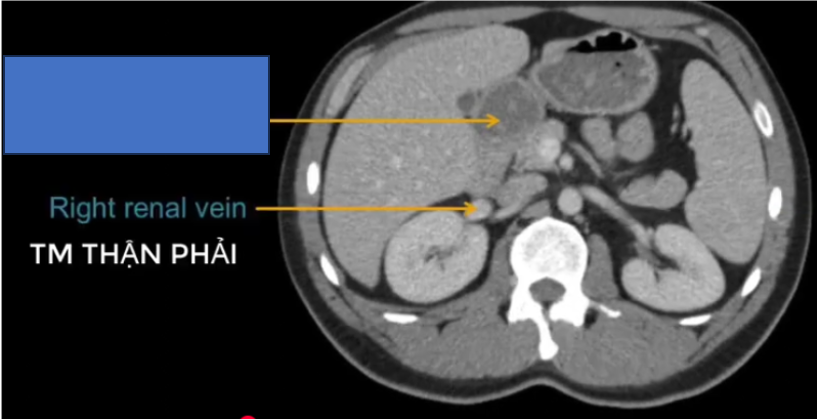

cq trong hình ?